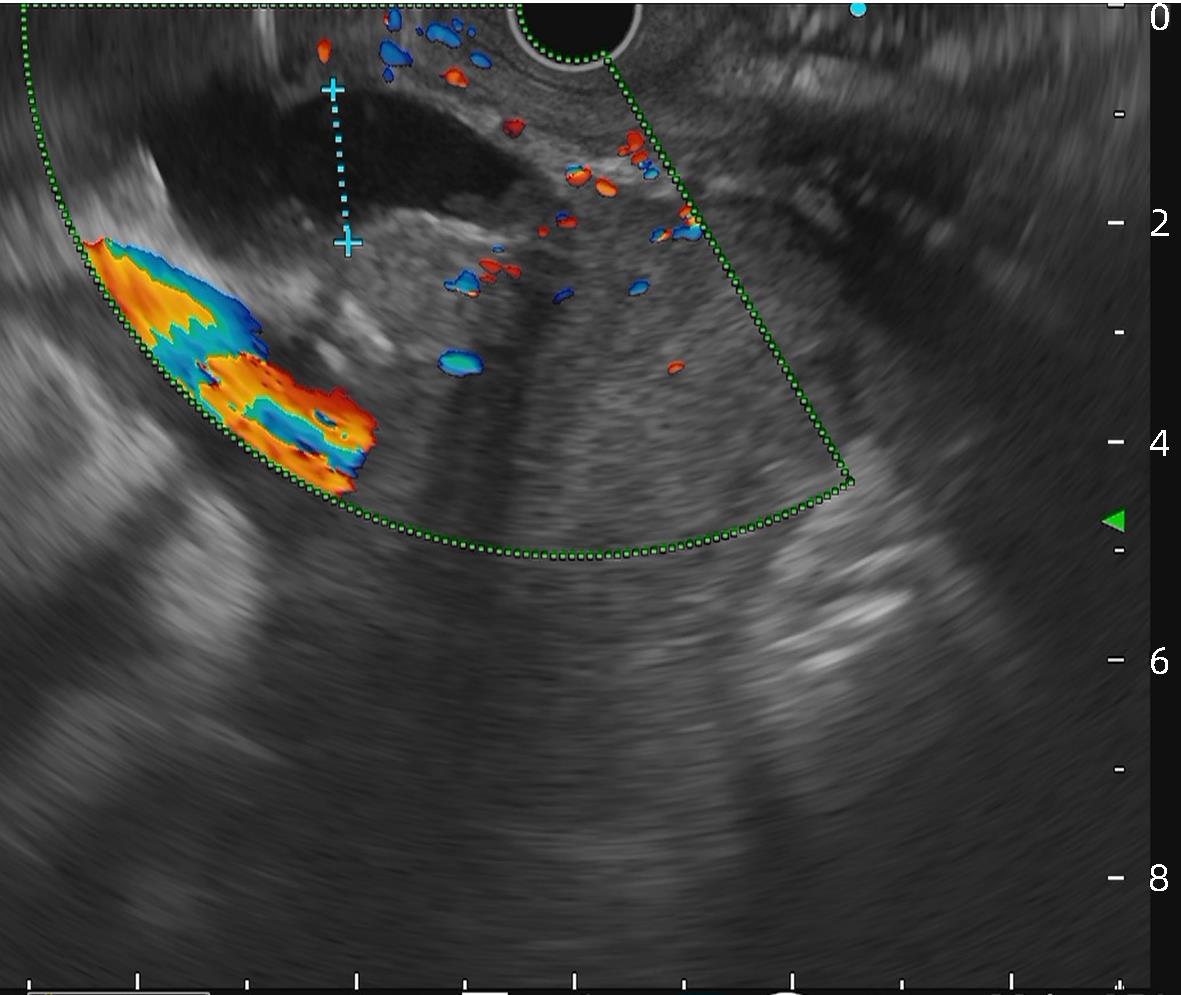

金属夹辅助内镜超声引导组织胶注射治疗合并胃肾分流的肝硬化胃静脉曲张患者的效果初探

马佳丽, 艾正琳, 胡居龙, 蒋煜, 周玉玲, 梁秀霞, 魏红山, 李坪

2024, 40(4): 734-738. DOI: 10.12449/JCH240415

摘要(1108) HTML (309) PDF (1036KB)(60)

摘要:

目的  探讨金属夹辅助内镜超声引导组织胶注射治疗合并胃肾分流的胃静脉曲张患者的效果及安全性。  方法  纳入2023年2月—2023年6月因肝硬化伴胃静脉曲张于首都医科大学附属北京地坛医院就诊,证实存在胃肾分流(GRS),并接受金属夹辅助内镜超声引导组织胶注射治疗的患者。主要的评价指标是术后曲张静脉减轻或消失情况,次要评价指标为手术完成情况及并发症。  结果  共11例合并GRS的胃静脉曲张患者纳入研究,男7例,女4例;中位年龄55岁;肝功能Child-Pugh A级1例,Child-Pugh B级7例,Child-Pugh C级3例;分流道最大直径(中位)8 mm,最小直径(中位)4 mm。治疗前靶血管血流中位流速11 cm/s,金属夹阻断后靶血管中位流速5 cm/s;中位组织胶使用量2 mL,聚桂醇使用量均为1 mL。所有患者手术结束后血流信号100%消失,手术成功率100%。随访6周患者均无再出血发生。术后1个月复查胃镜示静脉曲张根除或基本消失9例,静脉曲张改善2例。  结论  对于合并GRS的胃静脉曲张肝硬化患者,金属夹辅助内镜超声引导组织胶注射治疗是一种可行,安全,有效的方法。